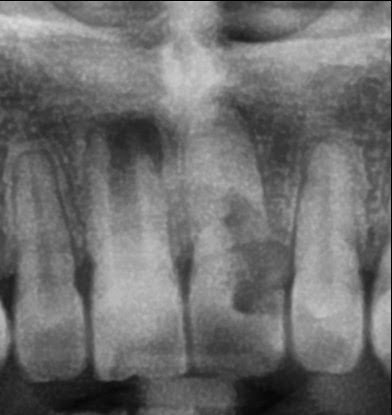

Caso Radiográfico N° 02: Seudo-infantilismo pulpar y resorción radicular externa asociado a antecedente traumático

Paciente de 20 años de edad de sexo masculino, que acude a nuestra institución para descartar caries con compromiso pulpar en pieza 2.1.

A la evaluación de la radiografía panorámica, observamos que la pieza 1.1 presenta desarrollo radicular incompleto caracterizado por cámara pulpar, conducto radicular y foramen apical amplios, compatible con seudo-infantilismo pulpar. Proceso osteolítico periapical de límites definidos compatible con granuloma periapical.

“El cuadro radiológico particular denominado seudo-infantilismo pulpar es propio de adolescentes. Se presenta casi exclusivamente en los dientes antero-superiores y es de origen traumático. Sus características radiográficas son las siguientes: La imagen de un diente permanente que ha hecho erupción y que presenta un desarrollo radicular incompleto; su cámara, su conducto y su foramen aparecen considerablemente amplios, como corresponde a un diente en vías de desarrollo”, contrastando con la formación completa o casi completa de los demás dientes permanentes. 1.